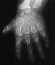

Hand deformities are essential for diagnosis and they are present

in almost 100% of cases. Hands are short and broad and deviated because

of the ulnar shortness. PIP joint stiffness is in contrasts with the hypermobility

of the thumb that is abducted over a short first metacarpal ("hitch-hiker"

deformity).

- Tubular bones in hands and feet are short and broad with typical deformities

in first metacarpal and in metatarsals